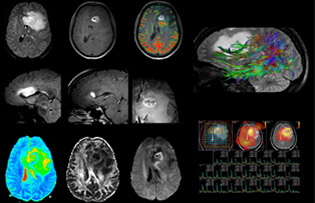

Umfangreiche Untersuchung beantwortet komplexe Fragestellungen bei Gehirntumor

Dr. Savatovsky nutzt fünf oder sechs verschiedene ExamCards für die Bildgebung einer Raumforderung oder eines bekannten Tumors im Gehirn. „Wenn eine Raumforderung im Gehirn vorliegt, versuchen wir diese zu charakterisieren, um dem Neurologen die Informationen zur Festlegung des nächsten Schrittes zu liefern bzw. den Neurochirurgen bei der Vorbereitung eines Eingriffs oder einer Biopsie zu unterstützen. Für die Untersuchung nach einer Behandlung verfügen wir je nach Therapieform über verschiedene Protokolle und wir verfolgen spezifische Ansätze bei intra- und extraaxialen Tumoren.“ „Dies ist die umfassendste Untersuchung, die wir durchführen. Ingenia liefert aufgrund der guten räumlichen Auflösung und des hohen Signal-Rausch-Verhältnisses alle diese Daten. Ausserdem ist das System so flexibel, dass damit kürzere Sequenzen möglich sind. Somit sind wir in der Lage, eine sehr umfangreiche Untersuchung in begrenzter Zeit vorzunehmen.“

„Die grösste Herausforderung besteht in der sachgemässen Charakterisierung der Läsion und der angemessenen Information des Chirurgen, zum Beispiel was die Position der Gefässe und der funktionellen Bereiche betrifft. Gelegentlich ist eine sehr umfassende Untersuchung notwendig, beispielsweise wenn eine Raumforderung an einem anderen Krankenhaus festgestellt wurde und der Patient anschliessend an uns überwiesen wurde. Wir führen dann eine Charakterisierung der Läsion und eine präoperative Bildgebung in einer Untersuchung durch, d.h. sowohl eine morphologische als auch eine funktionelle Beurteilung. Für die morphologische Beurteilung verwenden wir eine T1-gewichtete Prä- und Postkontrastbildgebung sowie FLAIR für die Beurteilung der Infiltration und Diffusion. Für die funktionelle Charakterisierung führen wir eine Perfusionsbildgebung, eine MR-Spektroskopie und eine suszeptibilitätsgewichtete Bildgebung durch, um Mikrogefässe oder Mikroblutungen innerhalb der Läsion aufzuspüren[4]. Für die präoperative Untersuchung führen wir eine spezifische morphologische Bildgebung durch, die mit dem Navigationssystem kompatibel ist. Je nach Position des Tumors erfolgt fMRT oder TDI.“